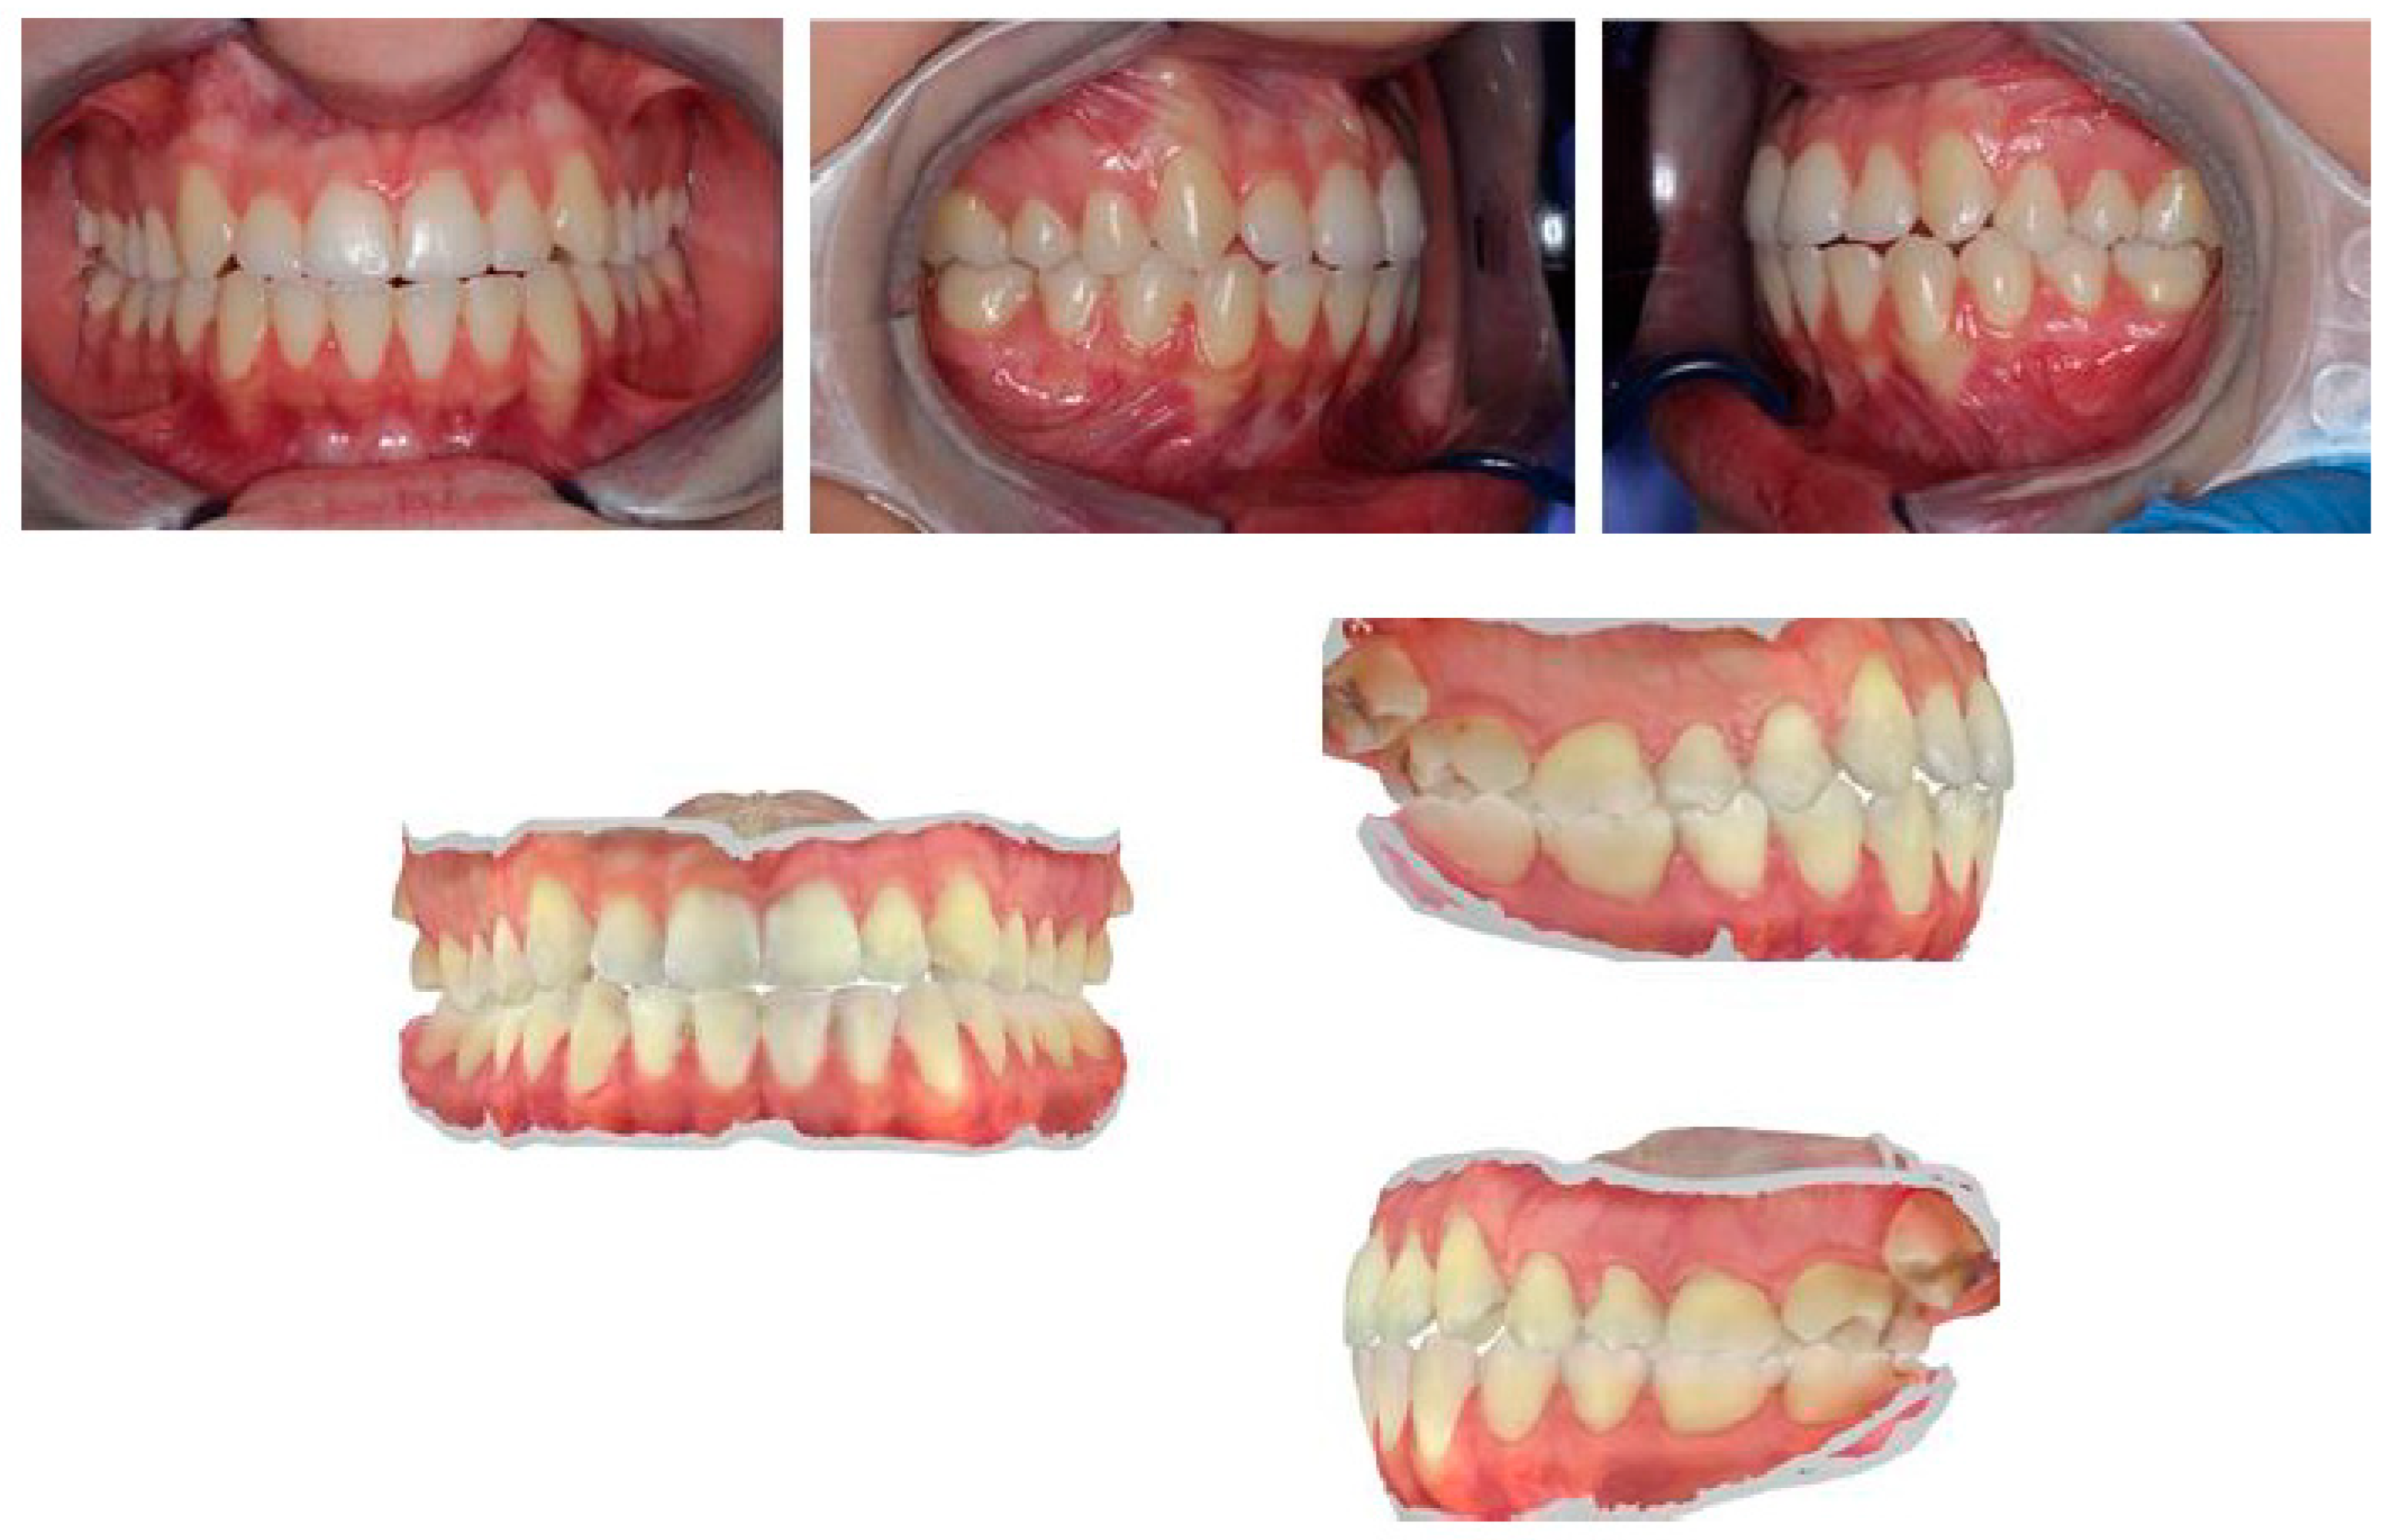

A 35-year-old male came to our attention due to pain in the posterior dental sectors and TMJ area, which started about 6 months prior. The pain was initially episodic and then became continuous. Medical history revealed that the patient was suffering from headaches, episodes of dizziness, and psychological complaints due to anxiety. The patient reported habitual grinding. The extraoral view is shown in Figure 24.

Intraoral views are shown in Figure 25, and Figure 26 reports orthopantomography: the absence of element 26, implant-prosthesis of element 31, and condylar asymmetry. It was indicated to investigate the diagnostic with an X-ray of elements 3.6 and 4.6.

Figure 25. Intraoral views show increased overbite (4–5 mm), overjet of about 1 mm, class I molar on the right, class II canine on the right, and class I canine on the left. There is evidence of widespread wear facets and a mild gingival recession on tooth 33.